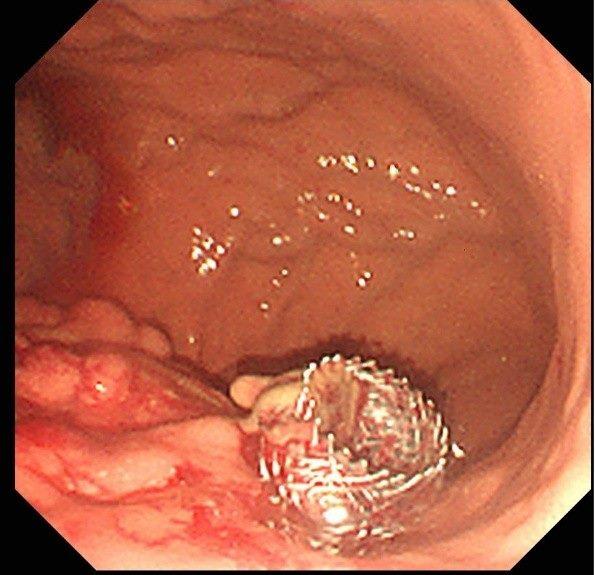

一位40歲的男性,因家族性遺傳高血脂症導致反覆性胰臟炎。今年八月,他再度因嚴重壞死性胰臟炎復發,合併呼吸衰竭、腎衰竭與敗血性休克,情況一度危急。經北市聯醫和平婦幼院區醫療團隊悉心照護,成功將病患從加護病房轉出,感染也逐步控制。然而,胰臟炎併發症形成的假性囊腫與膿瘍卻成為後續治療的棘手挑戰。在經過六周的抗生素治療後,消化內科主治醫師黃柏翰於今年九月攜手內視鏡室團隊,為這位病患成功執行臺北市立聯合醫院體系第一例的內視鏡超音波導引下胰臟膿瘍金屬支架引流術。

這項微創手術透過內視鏡,將金屬支架精準地放置於胰臟病灶處並與胃內建立引流通道,有效排出壞死組織或囊液,成功避免了傳統外科手術的巨大創傷與高風險,為病患帶來治療新希望。

黃柏翰表示,這項新技術的成功,代表和平婦幼院區在處理複雜胰臟疾病的能力已邁入新里程碑。藉由內視鏡超音波精準定位後金屬支架的置放,能以更安全、更有效的方式,幫助那些因胰臟炎併發症而飽受折磨的病患。

(照片由黃柏翰醫師提供,卡通圖引用自Tae Jun Song, Sang Soo Lee, Jong Ho Moon, Hyun Jong Choi, Chang Min Cho, Kwang Hyuck Lee, Se Woo Park, Seong-Hun Kim, Seung Ok Lee, Yun Nah Lee, Jong Kyun Lee, Efficacy of a novel lumen-apposing metal stent for the treatment of symptomatic pancreatic pseudocysts (with video), Gastrointestinal Endoscopy, Volume 90, Issue 3, 2019, Pages 507-513, ISSN 0016-5107,)